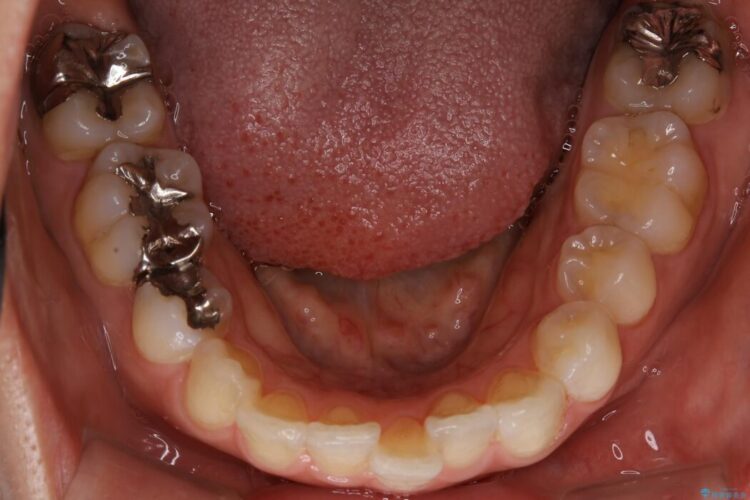

抜歯矯正後の後戻りについてご相談にいらした患者様です、

後戻りの程度としては軽度なので、治療期間としては短く終えることが出来ました。

前歯の正中線も改善され大変満足していただきました。